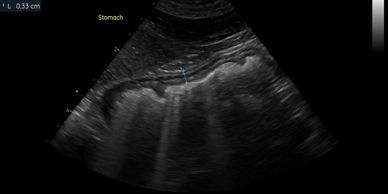

An evaluation of every abdominal organ for size, margination, echotexture, and neoplasia. All standard abdominal measurements will be acquired according to the current ACVR protocol

Screening of the gastrointestinal tract for foreign material

Evaluation and measurements of the intestinal wall layers. Includes screening for intestinal masses, inflammatory disease, and gastrointestinal lymphoma